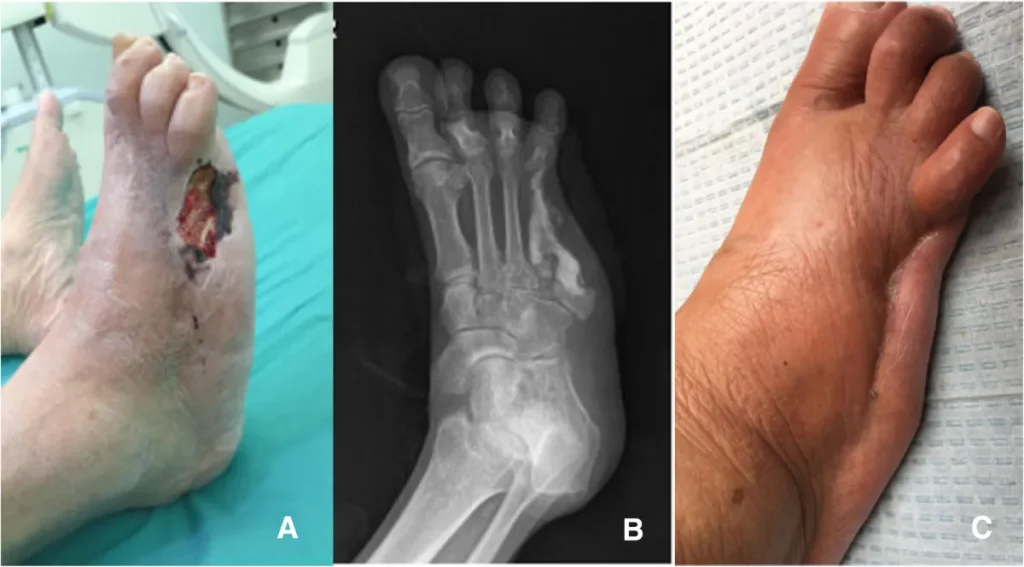

What is the success rate of Ilizarov treatment for bone infections?

Studies show that Ilizarov bone transport achieves 77% excellent to good bone healing results for infected nonunion cases. When combined with proper soft tissue reconstruction, infection eradication rates can reach 96.5%.

How long does treatment take?

Treatment duration varies from 6-12 months depending on infection severity and bone defect size. This includes surgical debridement, bone transport phases, and consolidation periods.